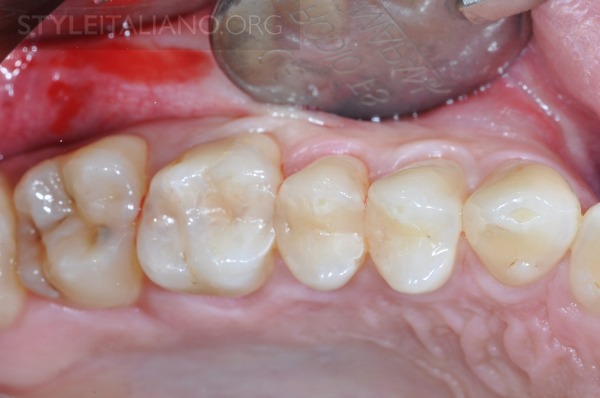

图1 麻醉后,治疗象限术前图